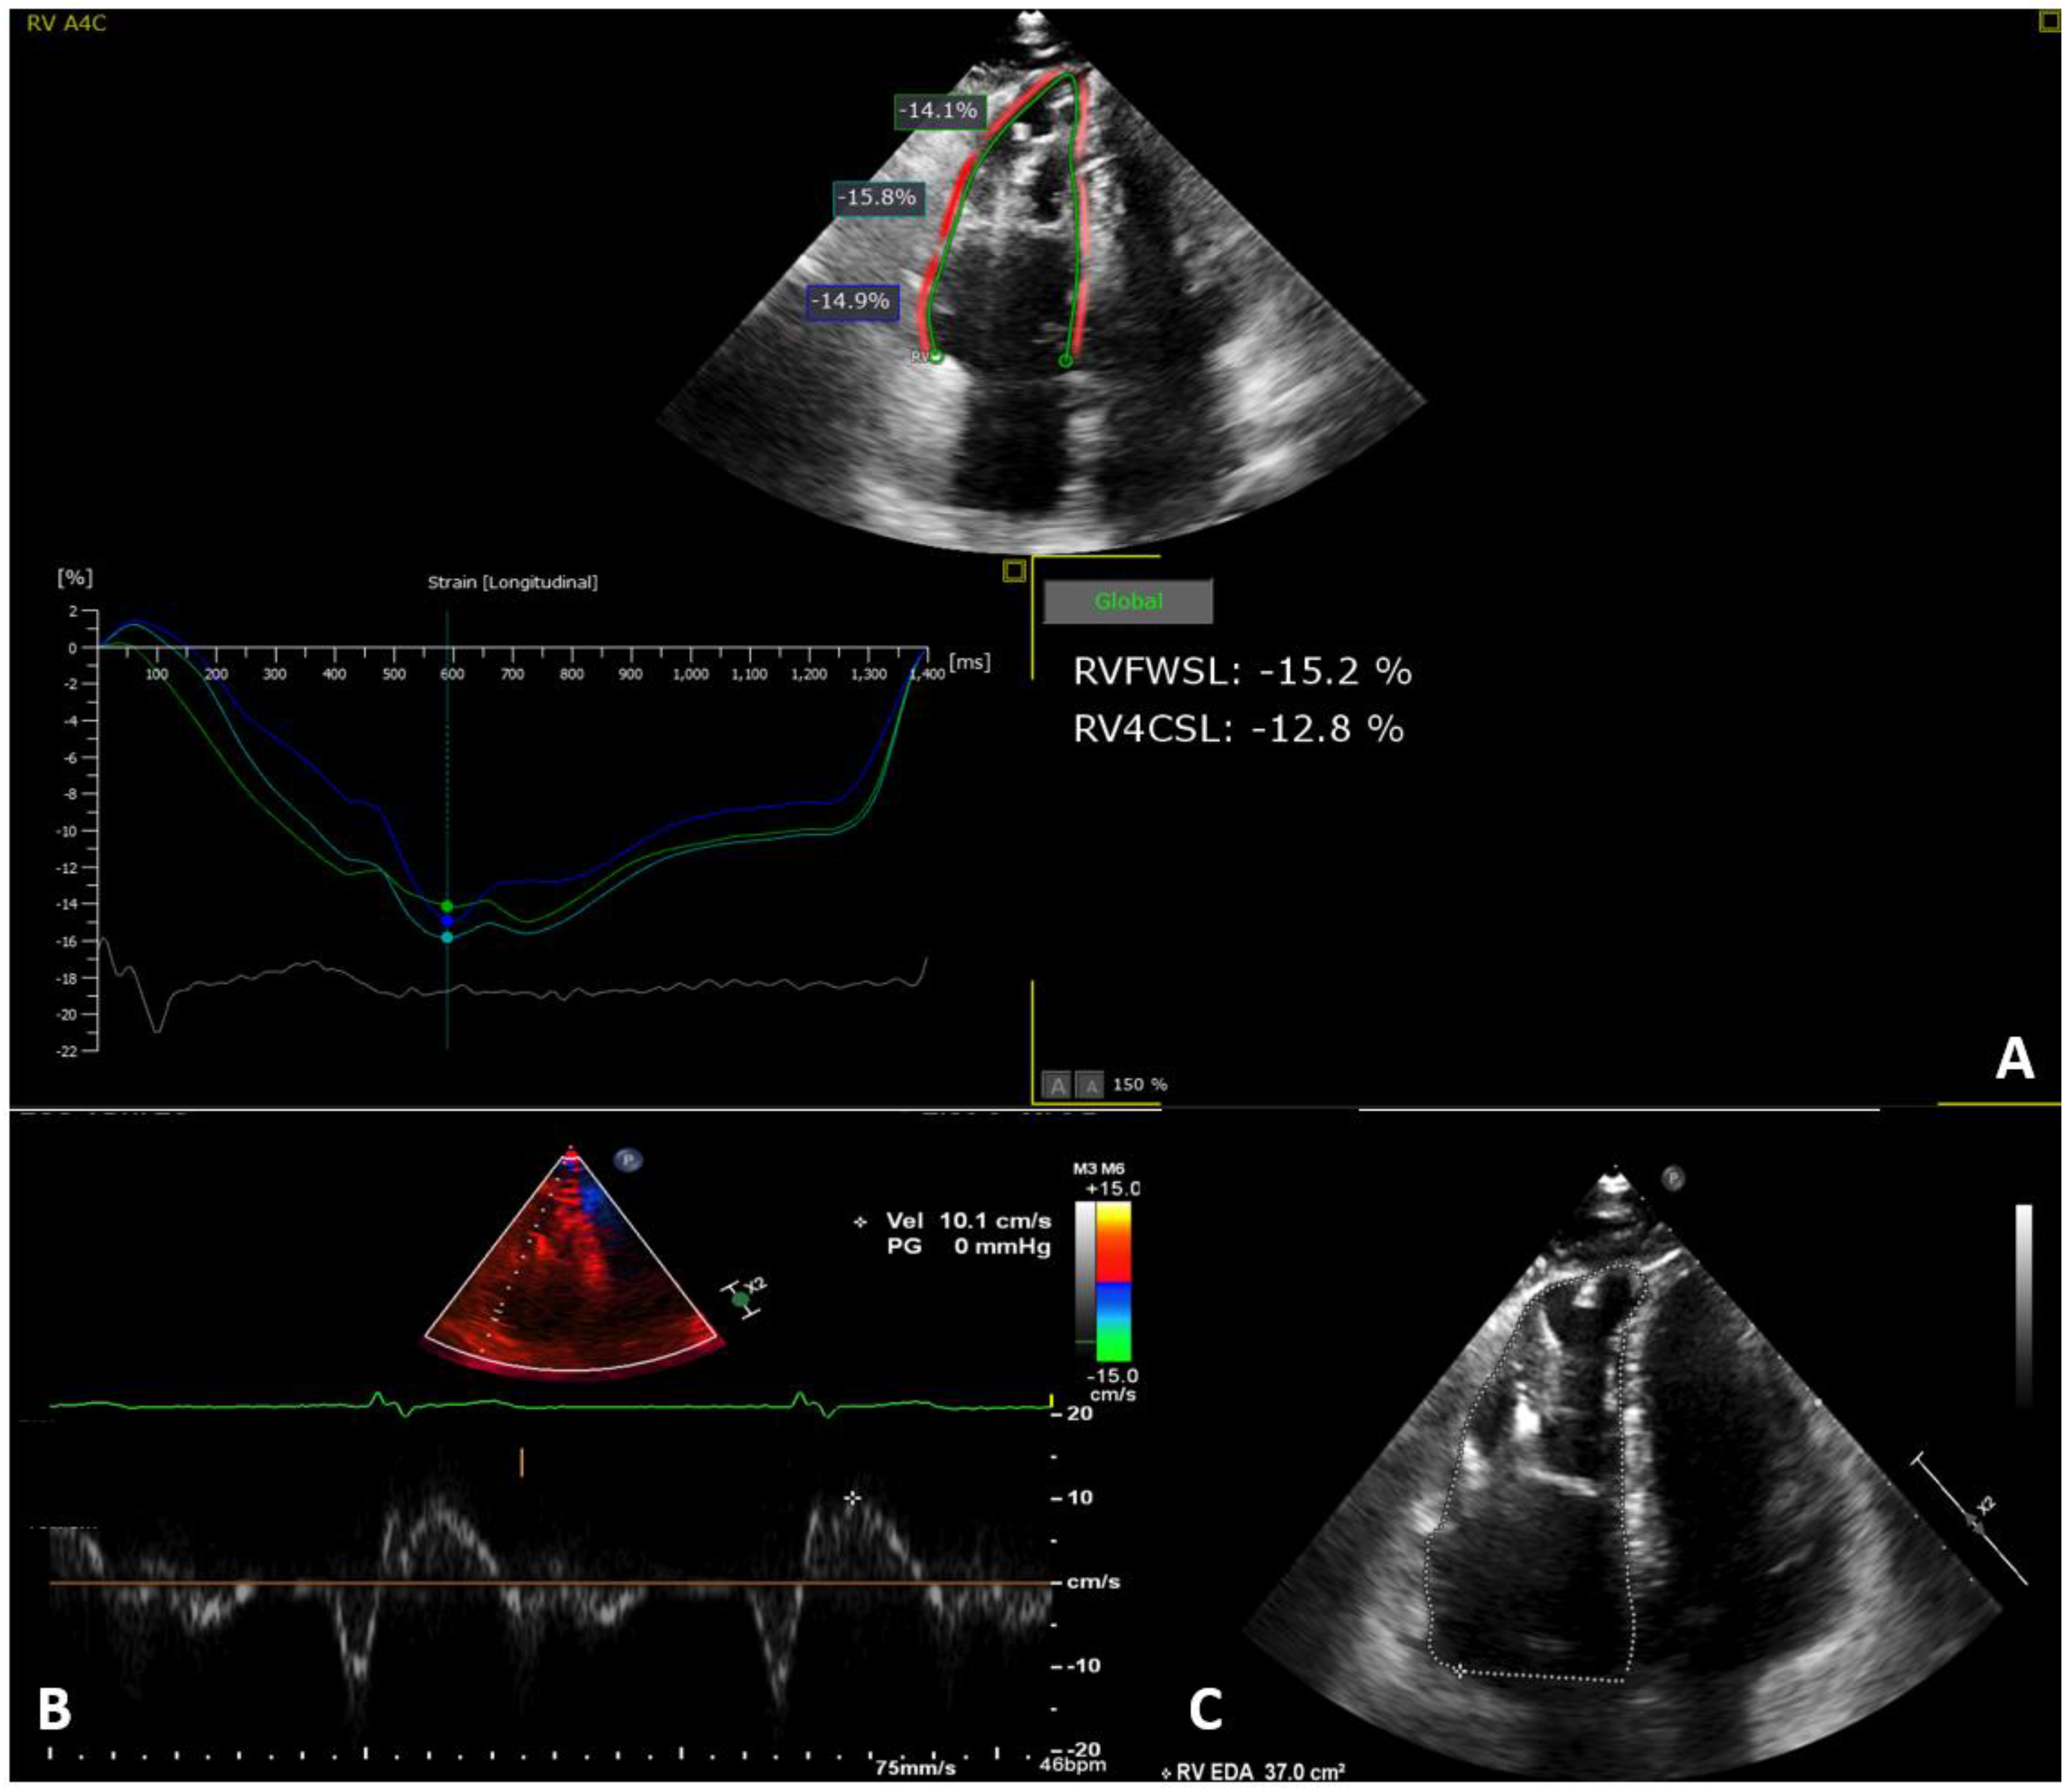

| −15.86 ± 4.25 |

| RVFWL Strain | −14.48 ± 3.85 | −17.24 ± 4.32 | 0.086 |